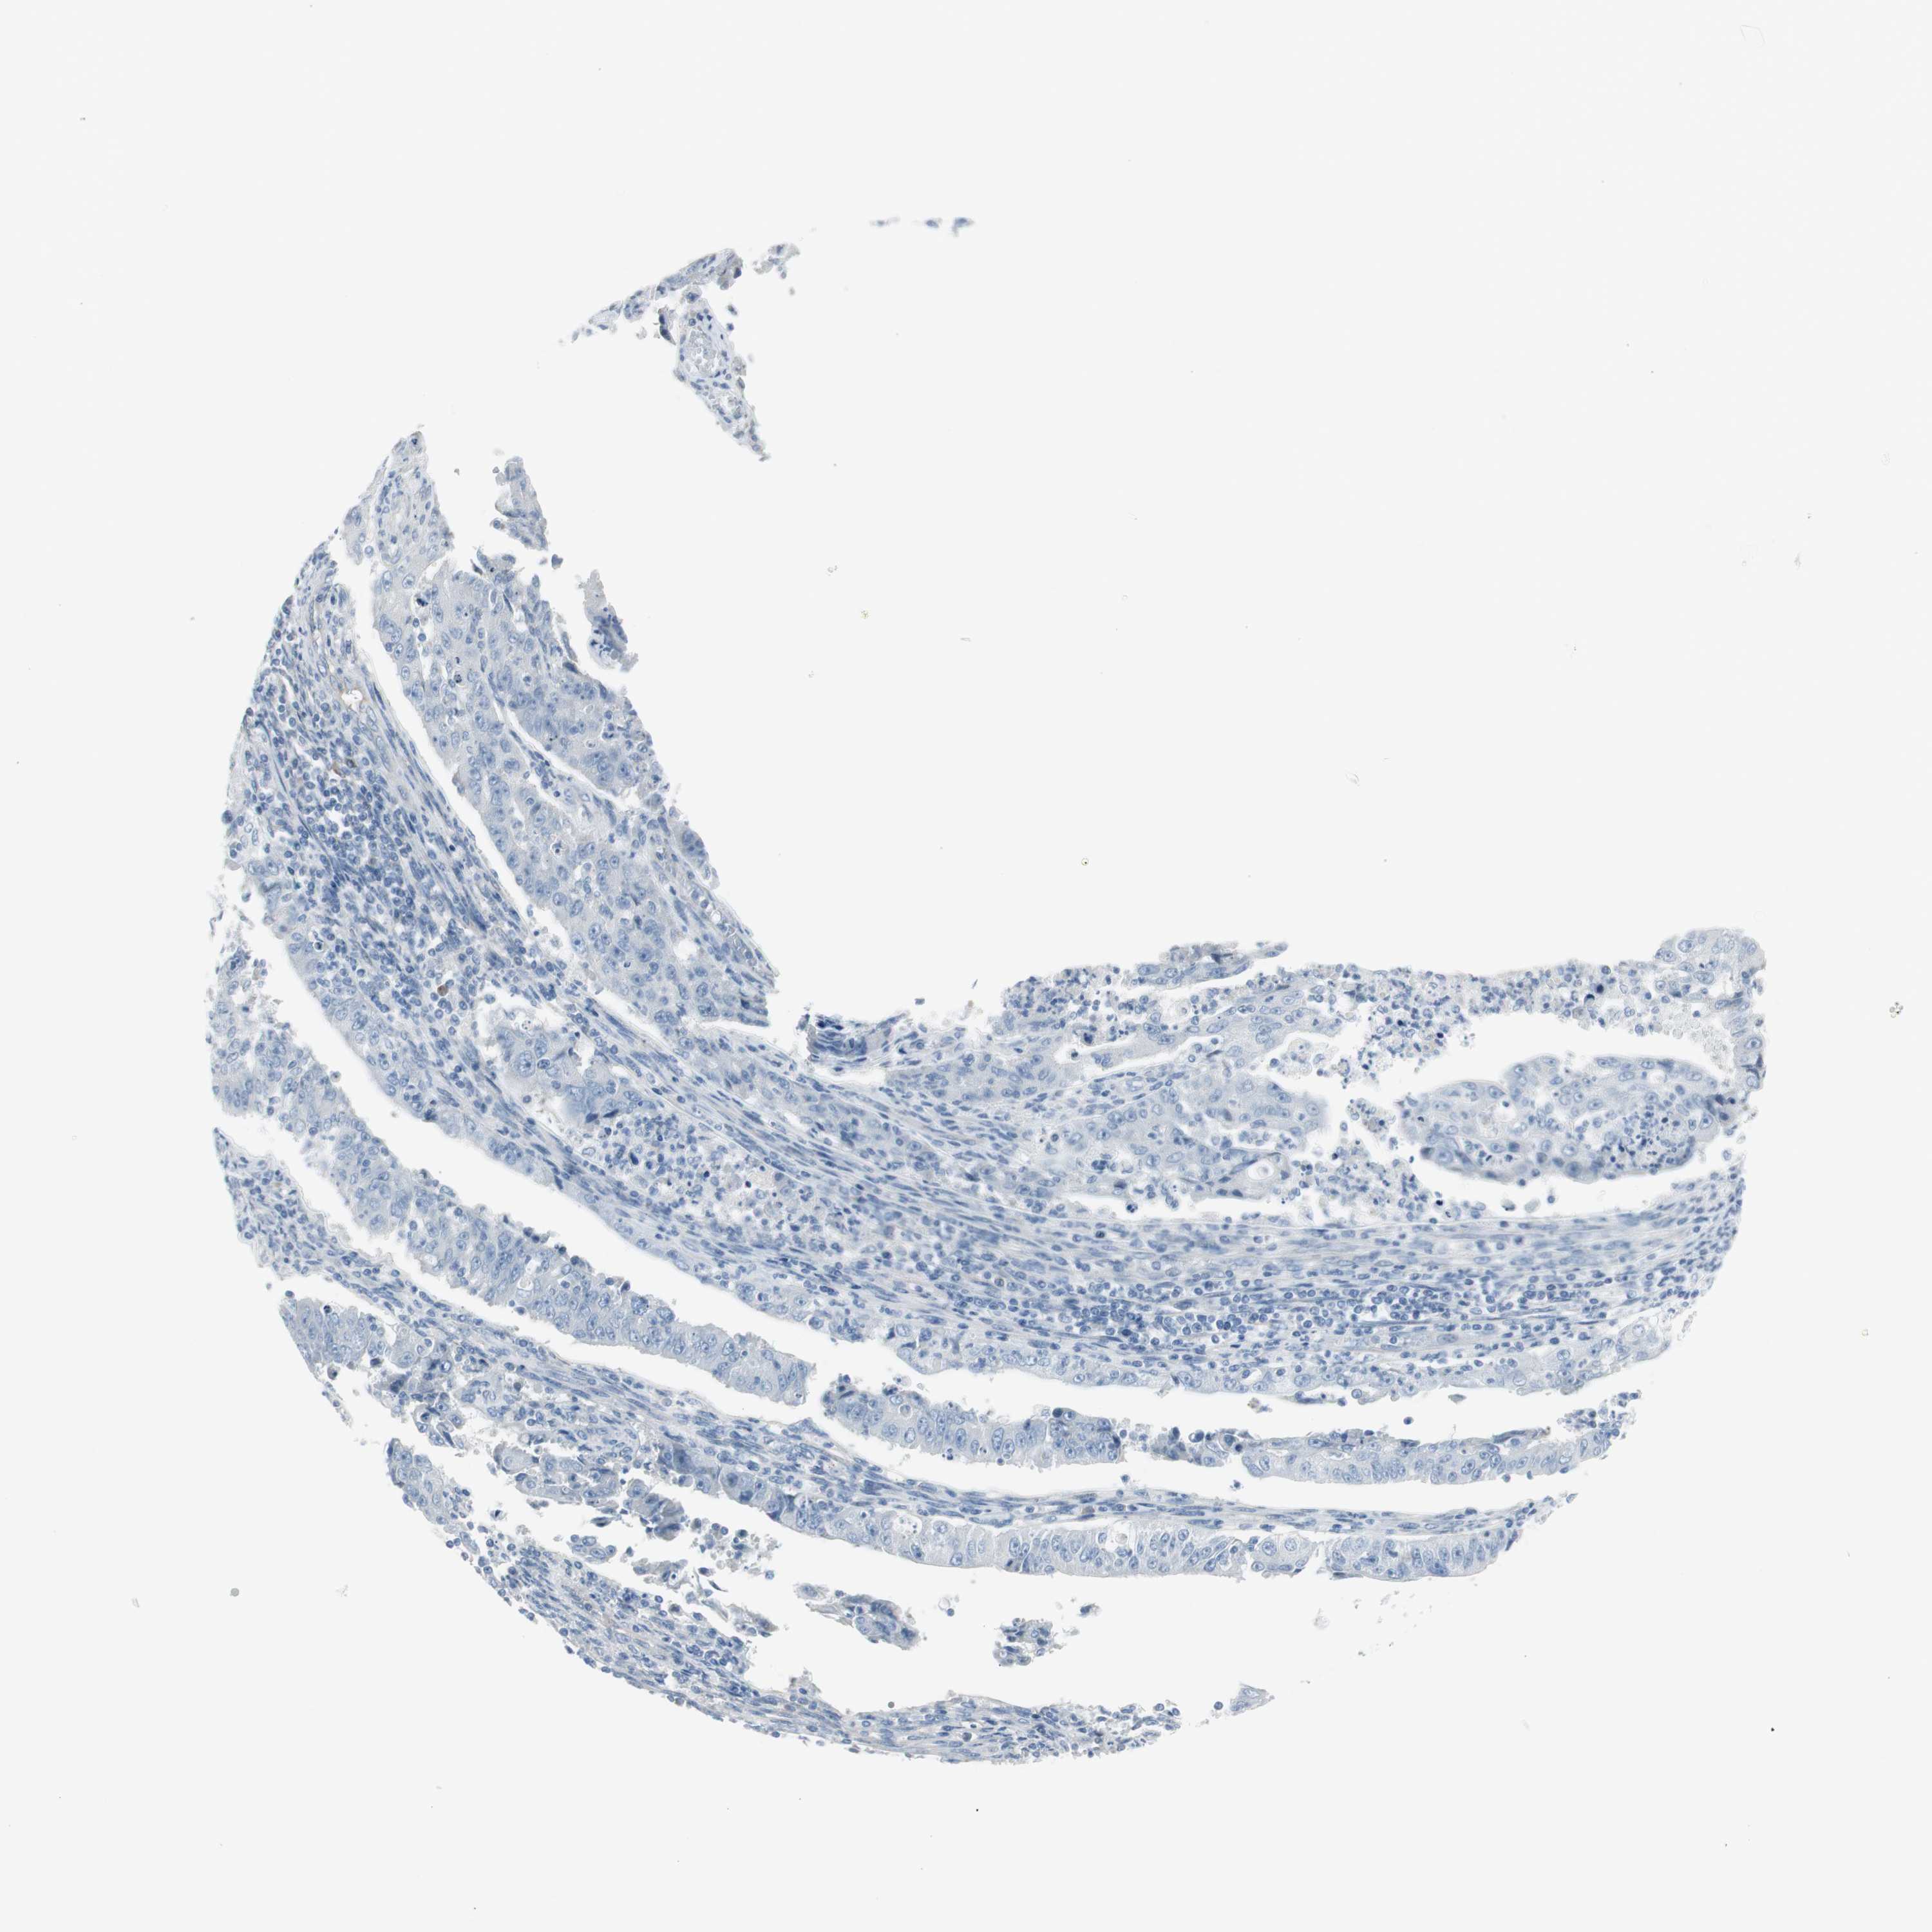

ENDOMETRIAL CANCER - Protein expressioni

A mouse-over function shows sample information and annotation data. Click on an image to view it in a full screen mode. Samples can be filtered based on level of antibody staining by selecting one or several of the following categories: high, medium, low and not detected. The assay and annotation is described here.

Note that samples used for immunohistochemistry by the Human Protein Atlas do not correspond to samples in the TCGA dataset.

Antibody stainingi

Antibody staining in the annotated cell types in the current human tissue is reported as not detected, low, medium, or high, based on conventional immunohistochemistry profiling in selected tissues. This score is based on the combination of the staining intensity and fraction of stained cells.

Each image is clickable and will lead to virtual microscopy that enables deeper exploration of all samples and also displays staining intensity scores, fraction scores and subcellular localization as well as patient and tissue information for each sample.

Antibody HPA008213

Antibody HPA008621